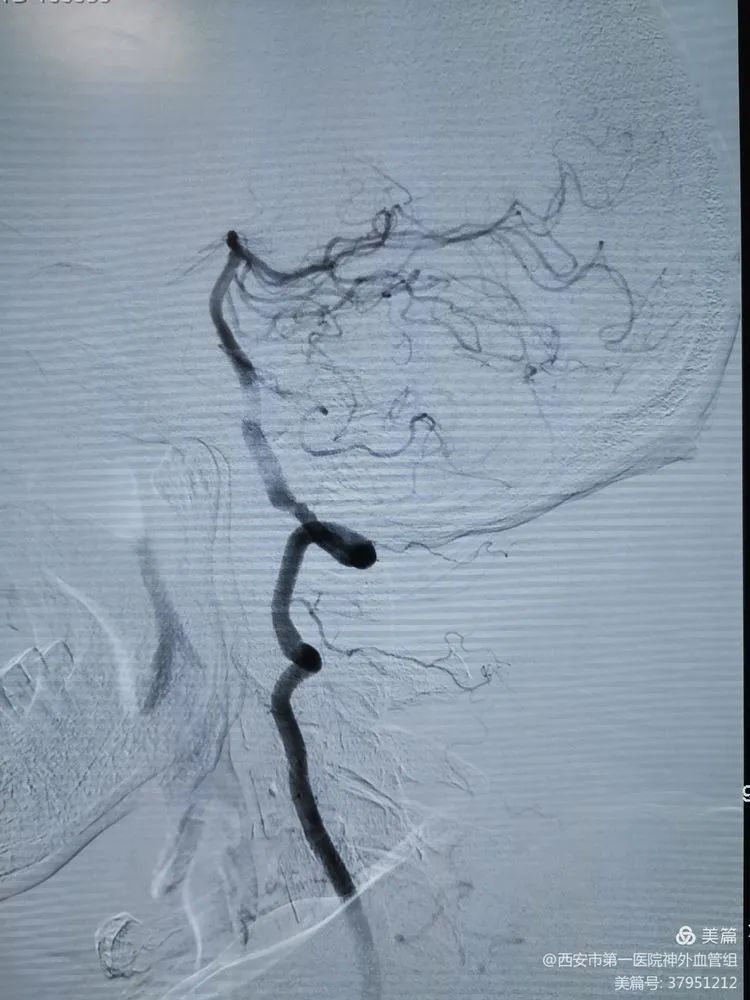

通过dsa全脑血管造影检查,发现患者右侧颈内动脉眼动脉段动脉瘤形成

大脑后动脉有少量代偿脑血管造影提示左侧大脑中动脉m1末端闭塞,大脑